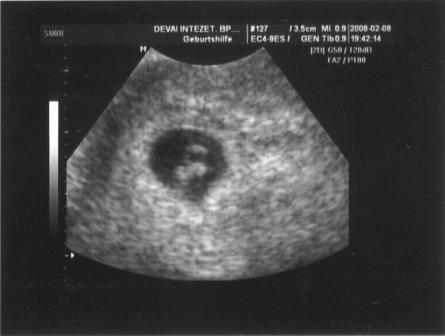

Amugy meg ngyon gondolkodom rola,hogy visszamegyek a korhazba es megkerem legalabb segitsenek a pe-resben meg a kilokodesben...es hatarozzak be a napjaim...

mert olyan nincs,hogy a baj nem a gyogyszerek miatt volt de mar nem hajlando tovabb kezelni a no

igen is jogom van a segitseghez es ha en nyarig nem akarok lombik babat segitse elo a termeszetes uthoz minden ami tole tellik

nem is ertem,hogy szakithattak csak igy meg

vgy lehet vallalom a befecskendezesest...

akkor tuti segitenek

vgy masik dokihoz megyek el van itt egy francia nogyogyasz na benne jobban bizok..mert mint irtam sajna a japan dokikhoz a kulfoldieknek nincs nagy bizalma semmilyen teren

de viszont o meg nem ismeri a leleteim meg semmi ilyet szal kicsit fejfajosabb a dolog de talan nyiltabban beszelne es maskepp is allna a dolgokhoz

na most ezen gondolkodom

lehet parommal beszelek errol mit gondol

ugy orulok neked es mar milyen szepen latni lehet

en is akarok ilyet